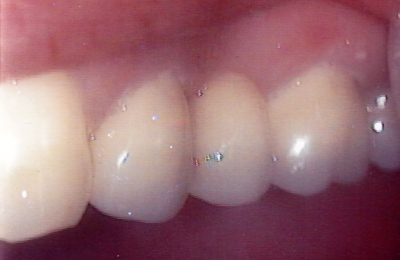

See the results

Drag the sliders below to see some of the amazing results achieved by other Lumino patients and our experienced team of dentists.

Bridge 1 Before Bridge 1 After